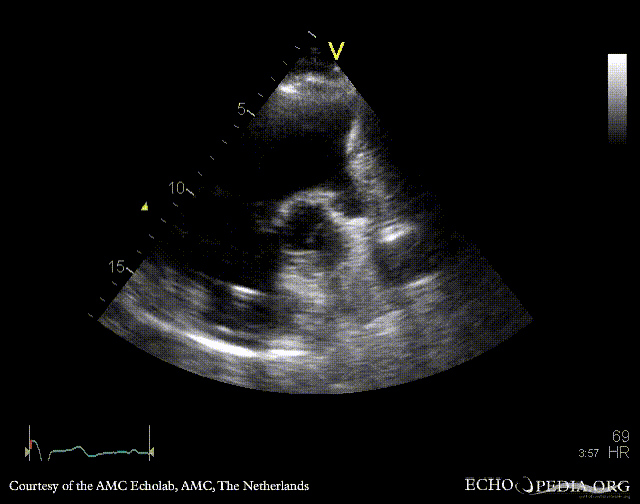

| PSAX: aneurysm of right ventricle outflow tract in patient with tetralogy of Fallot | |